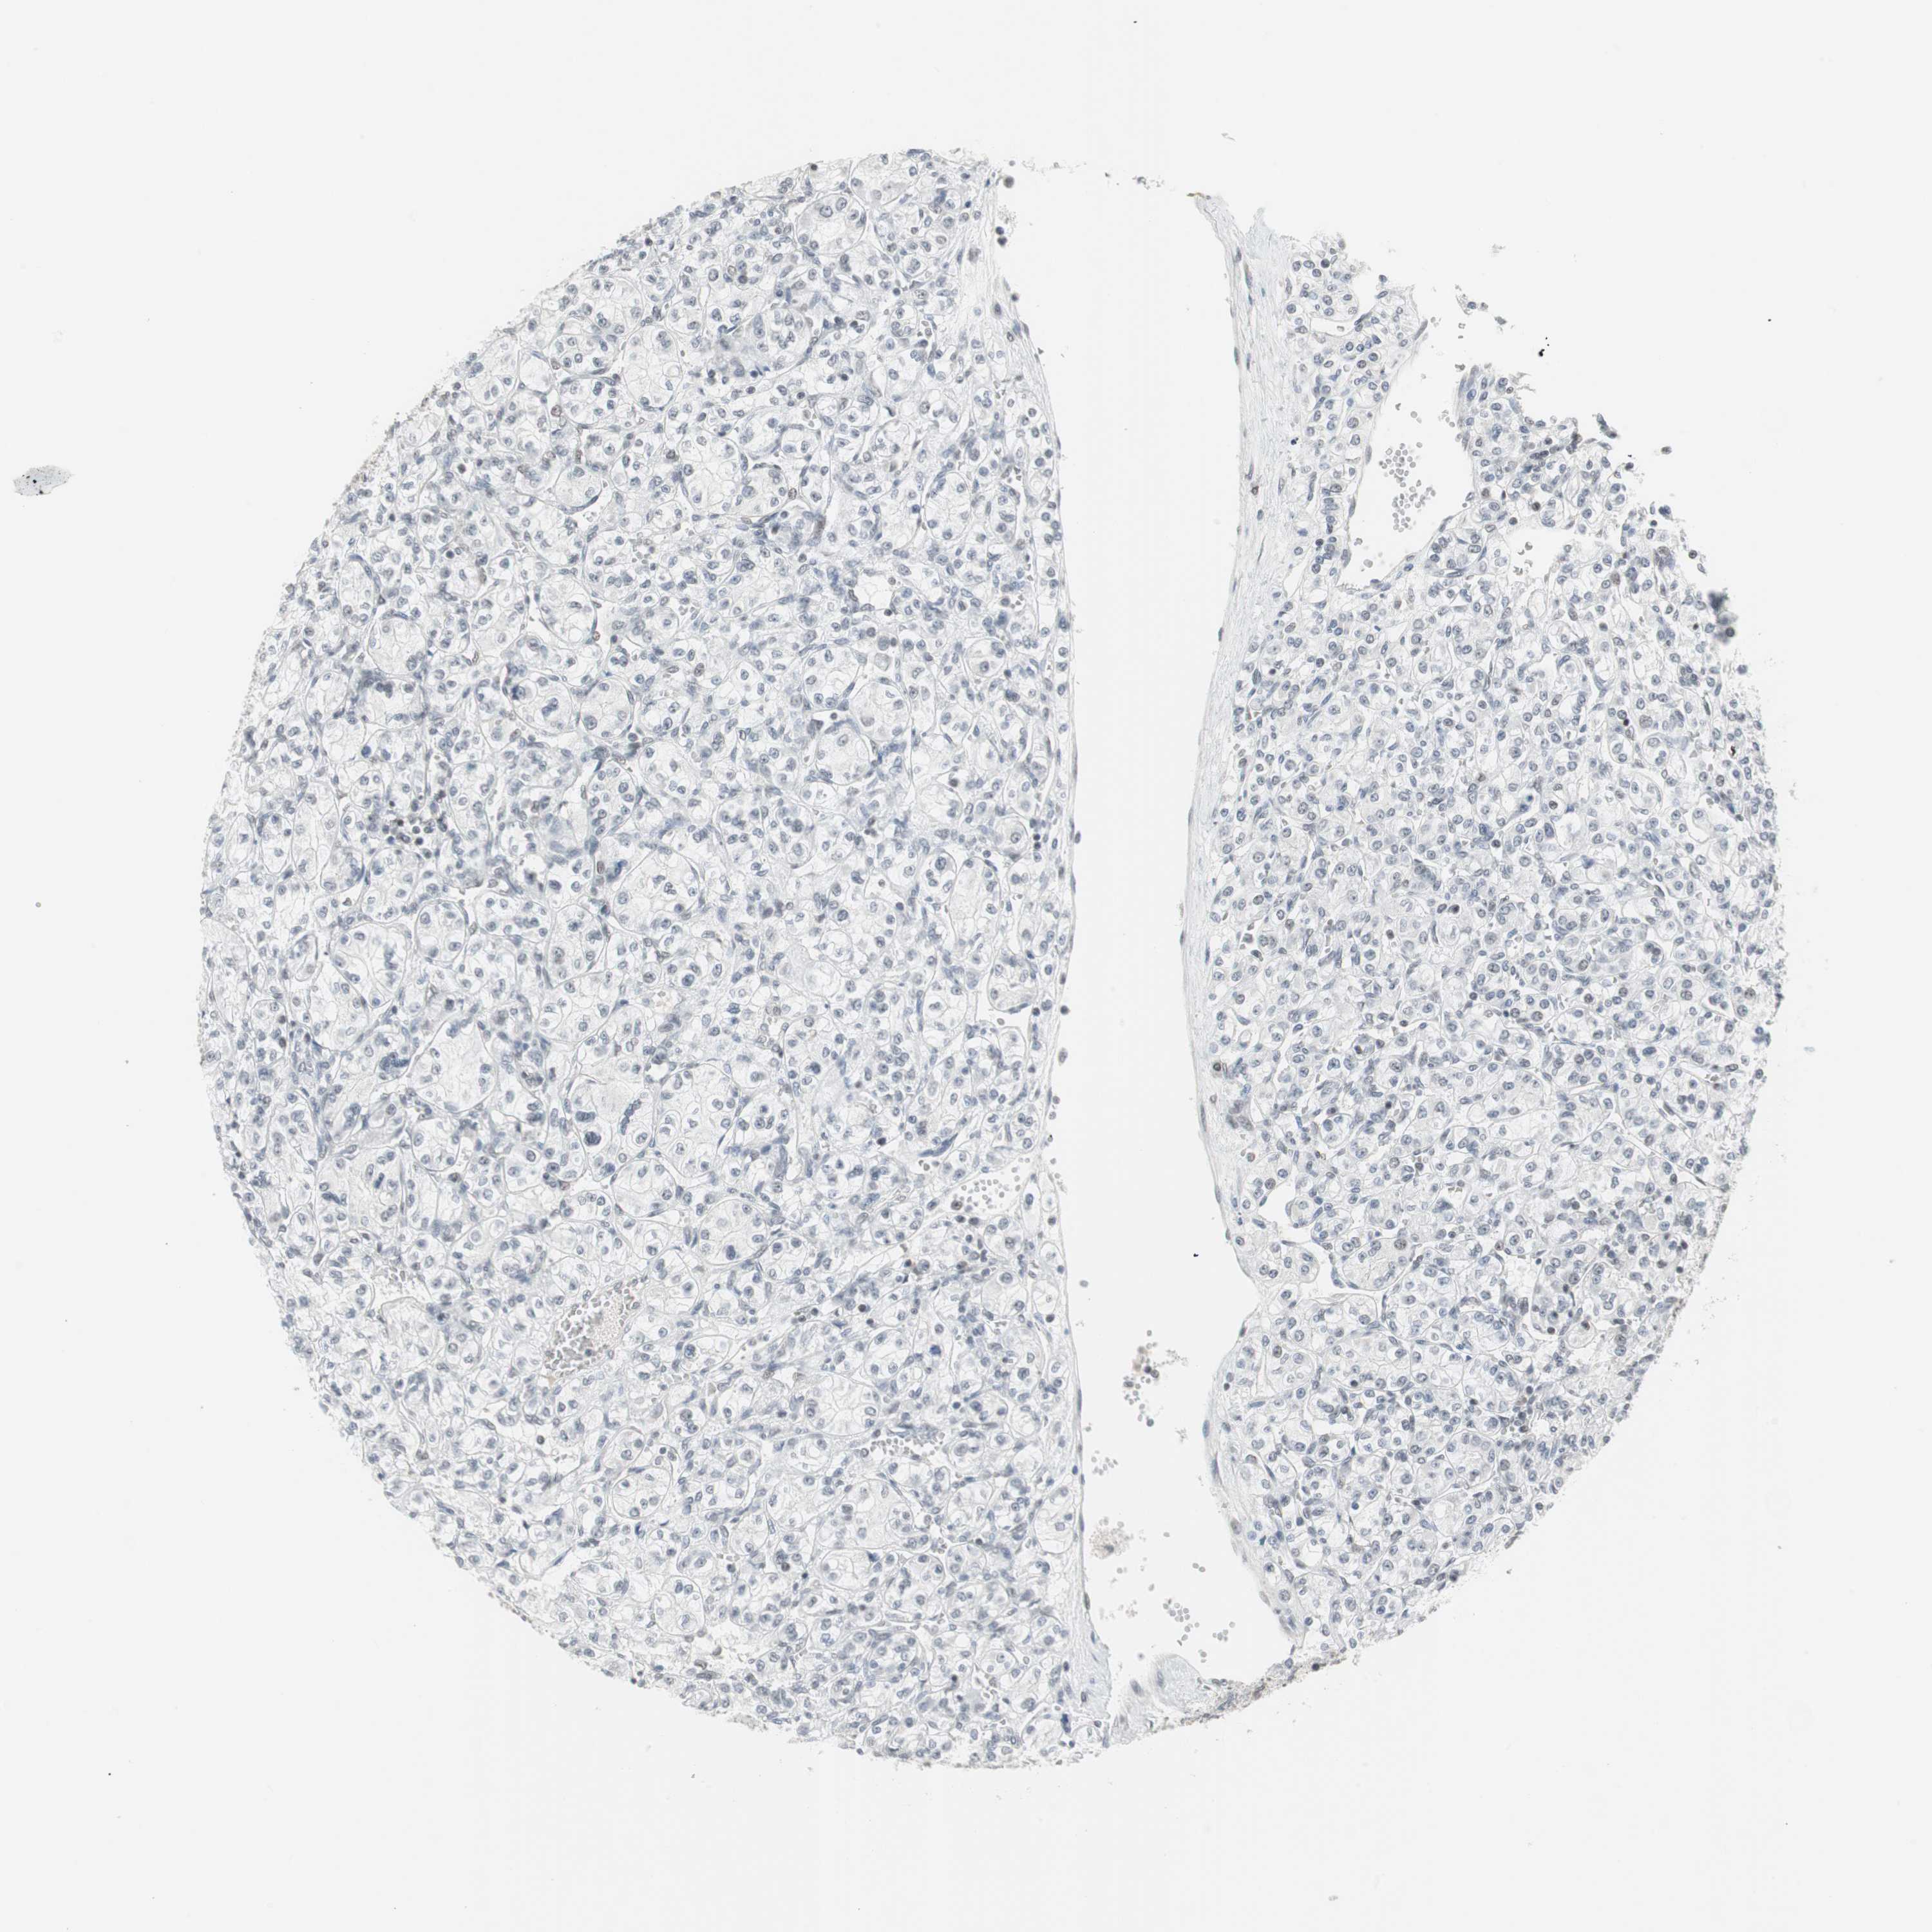

Renal cancer

Kidney chromophobe